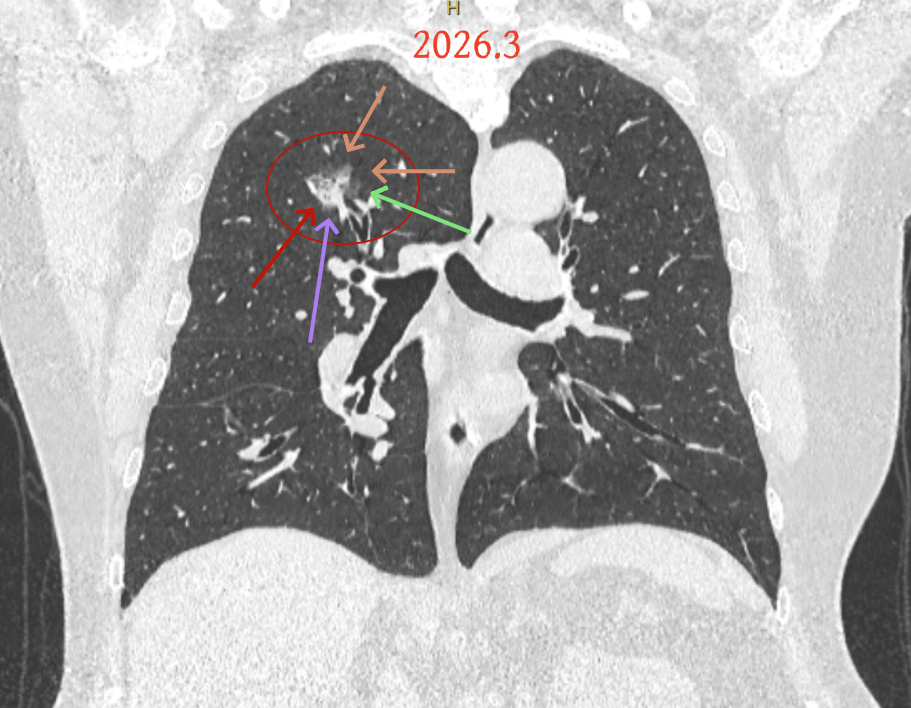

但病灶B却显然进展!变成以实性成分为主的了!

两处均有进展,混合密度这处更显著些。那要考虑手术了的。之前也有碰到较短时间内进展是伴炎症或纤维增生的,但我们不能赌。建议手术为宜。意见供参考!

再看病灶B的2026年3月细节影像特征:

边缘位置也是较淡的磨玻璃成分。

上图是混合密度,轮廓较清,瘤肺边界欠清晰。

病灶A以及他处磨玻璃结节其实进展都是不明显的,略与2022年比,病灶A稍显明显点。病灶B开始时极淡,之前进展虽有但也甚微,直到2025年9月仍是磨玻璃成分为主,只是点状少许密度稍高成分。但在最近半年内却显然进展!若从影像上判断,基本上就得是浸润性腺癌了。那有几点:一是必不能再随访;二是大小来看仍是1A期;三是从快速进展来说,可能含有部分高危亚型,比如微乳头或实体型等;四是他处的磨玻璃结节以及病灶A显然不能用病灶B的转移来解释,仍考虑是多原发早期肺癌。

结友问能否先穿刺?我是这么考虑的:你这个病灶B一是位置深,且靠近附近的血管,不容易穿刺;二是从影像变化来看,基本上肯定是恶性的,不是100%,也是95%以上的概率。刚才我又在重建看冠状位与矢状位以及各次影像,目前混合密度的其实是后来者居上,原来刚开始是它比旁边的病灶密度淡的,但它的密度不是太纯,前次你自己也说似乎有点状偏实性成分。只是最近这半年进展特别快。这说明它的恶性程度较它边上原来就比较明显的那处恶性程度高,亚型中大概率有低分化的成分。所以从目前的影像来看,要尽快手术,而且切肺叶更为稳妥些。

这是较为少见的一个病例,磨玻璃为主,而且一直瘤肺边界欠清晰的病灶何以会在之前三年均极缓慢微小变化的情况下,近半年却快速进展呢?从影像细节上看,我们能否进一步分析哪种纯磨玻璃结节可能会较快进展?结合本例,我个人的考虑是:1、病灶整体显得是磨玻璃密度,但灶内并不均匀,就如磨玻璃密度中混入细沙状;2、整体轮廓虽然较清但瘤肺边界相对来说却并不太清晰;3、邻近有血管紧挨,而且与病灶这间缺乏间隙;4、病灶密度不高,没有明显实性成分,却有灶内有细支气管通气征,说明肿瘤成分具有收缩力,却与纯磨的收缩不匹配(纯磨一般不太会有明显收缩力)。如果有上面这些特征可能要提高警惕,一是适当较短的随访间隔,二是影像细节变化要更加注意,开始变化意味着已经进入发展期,而非蛰伏期。当然是否在2025年9月时定得手术了?如果是孤立性的病灶B,且位置位于能简单楔形切除的位置,那是可以考虑的。但位置深、两肺多发,切除范围不小,再今年据肺癌诊疗指南中说的混合磨玻璃结节实性成分不足25%是非侵袭性病变,且几乎不会转移,那么按原则仍再随访显然是可以的。本例的随访变化再次表明磨玻璃密度肺癌的诊疗个体化之路仍是很漫长的,按指南原则的随访或诊疗显然不足以覆盖所有病例,总结与经验积累永远在路上。